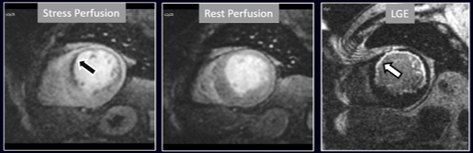

The aim of perfusion studies is the demonstration of a blunted increase—or a reduction—in regional MBF in response to a vasodilator stimulus which can be attributed to a flow-limiting coronary artery lesion. Rest perfusion studies alone are not useful in this sense, as basal MBF is kept within normal limits even in territories supplied by a severely stenosed vessel, and is only after a vasodilator agent has been given that the reduction in CFR can be evidenced [24]. In CMR studies, this situation is detected as a reduced increase in SI of the underperfused territories (Fig. 3).

Fig. 3.Induced perfusion defect. Subendocardial perfusion defect at the interventricular septum during stress (left panel, black arrow), not present at rest (middle panel), in a patient with significant coronary stenoses in the left anterior descending (LAD) artery (right panel, white arrows).